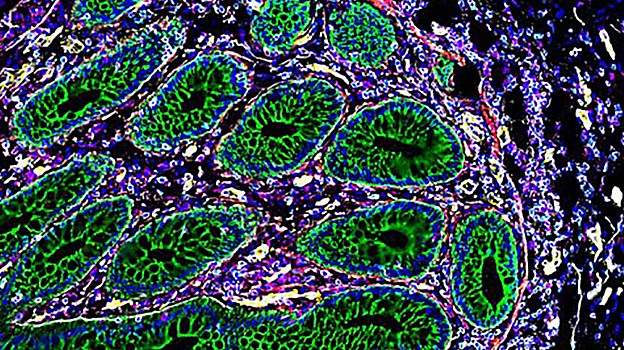

Estas herramientas se han utilizado para generar atlas de células de referencia para el intestino humano, el riñón y los tejidos conectados a la placenta. Este es solo el primer paso: en el futuro, los investigadores de HuBMAP continuarán recopilando, analizando y visualizando datos de organización celular para otros órganos humanos sanos, como la vejiga, los ojos, los órganos reproductivos femeninos, el corazón, la rodilla, los pulmones, los ganglios linfáticos, el páncreas, el bazo y el timo.

El intestino humano es un órgano complejo con muchas estructuras y funciones diferentes (desde la digestión hasta el apoyo al sistema inmunológico). En uno de los trabajos que se publican hoy en «Nature», los investigadores de la Universidad de Stanford (EE.UU.) analizaron ocho secciones del intestino de nueve individuos, gracias a lo cual hallaron importantes diferencias en la composición celular en las diferentes regiones. Los hallazgos revelan la composición celular compleja y variada que contribuye al funcionamiento de este órgano.

Así, identificaron nuevos subtipos de células epiteliales y descubrieron que diferentes tipos de células forman «vecindarios», algunos de los cuales están específicamente preparados para mediar respuestas inmunológicas.

El intestino absorbe los nutrientes de los alimentos y protege el cuerpo de las bacterias, al tiempo que mantiene un equilibrio saludable de las bacterias beneficiosas que ayudan a la digestión. Para realizar estas tareas, emplea una variedad de tipos de células, incluidas las células epiteliales que forman el revestimiento intestinal, las células del tejido conectivo, las células nerviosas y las células inmunitarias. Con los nuevos mapas, los científicos pudieron identificar dónde se encuentra cada tipo de célula y con qué tipo de células se asocian.